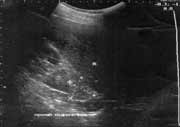

Размеры выявленных опухолей колебались от 2 до 10 см в диаметре. Все имели капсулу, гладкую поверхность, округлую или овальную форму. Небольшие опухоли имели однородную изоэхогенную структуру (Рис. 3), а в 4 случаях, когда размер опухоли превышал 4 см, внутренняя эхоструктура была представлена неравномерным чередованием участков повышенной и пониженной эхогенности за счет зон некроза, дегенеративных изменений и обызвествлений, что подтверждалось при гистологических исследованиях удаленных опухолей (Рис. 4, 5).

Рис. 3. Опухоль правого надпочечника с однородной структурой.